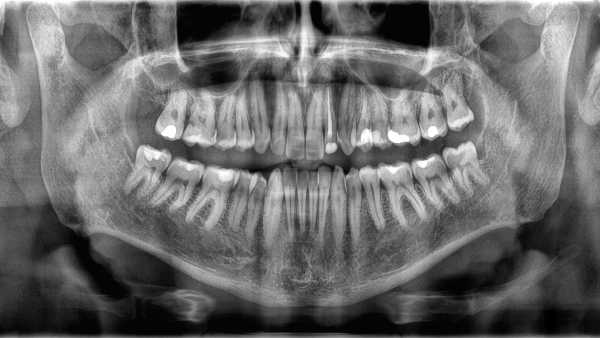

Why aren’t teeth considered bones?

—Why aren’t teeth recognized as bones?